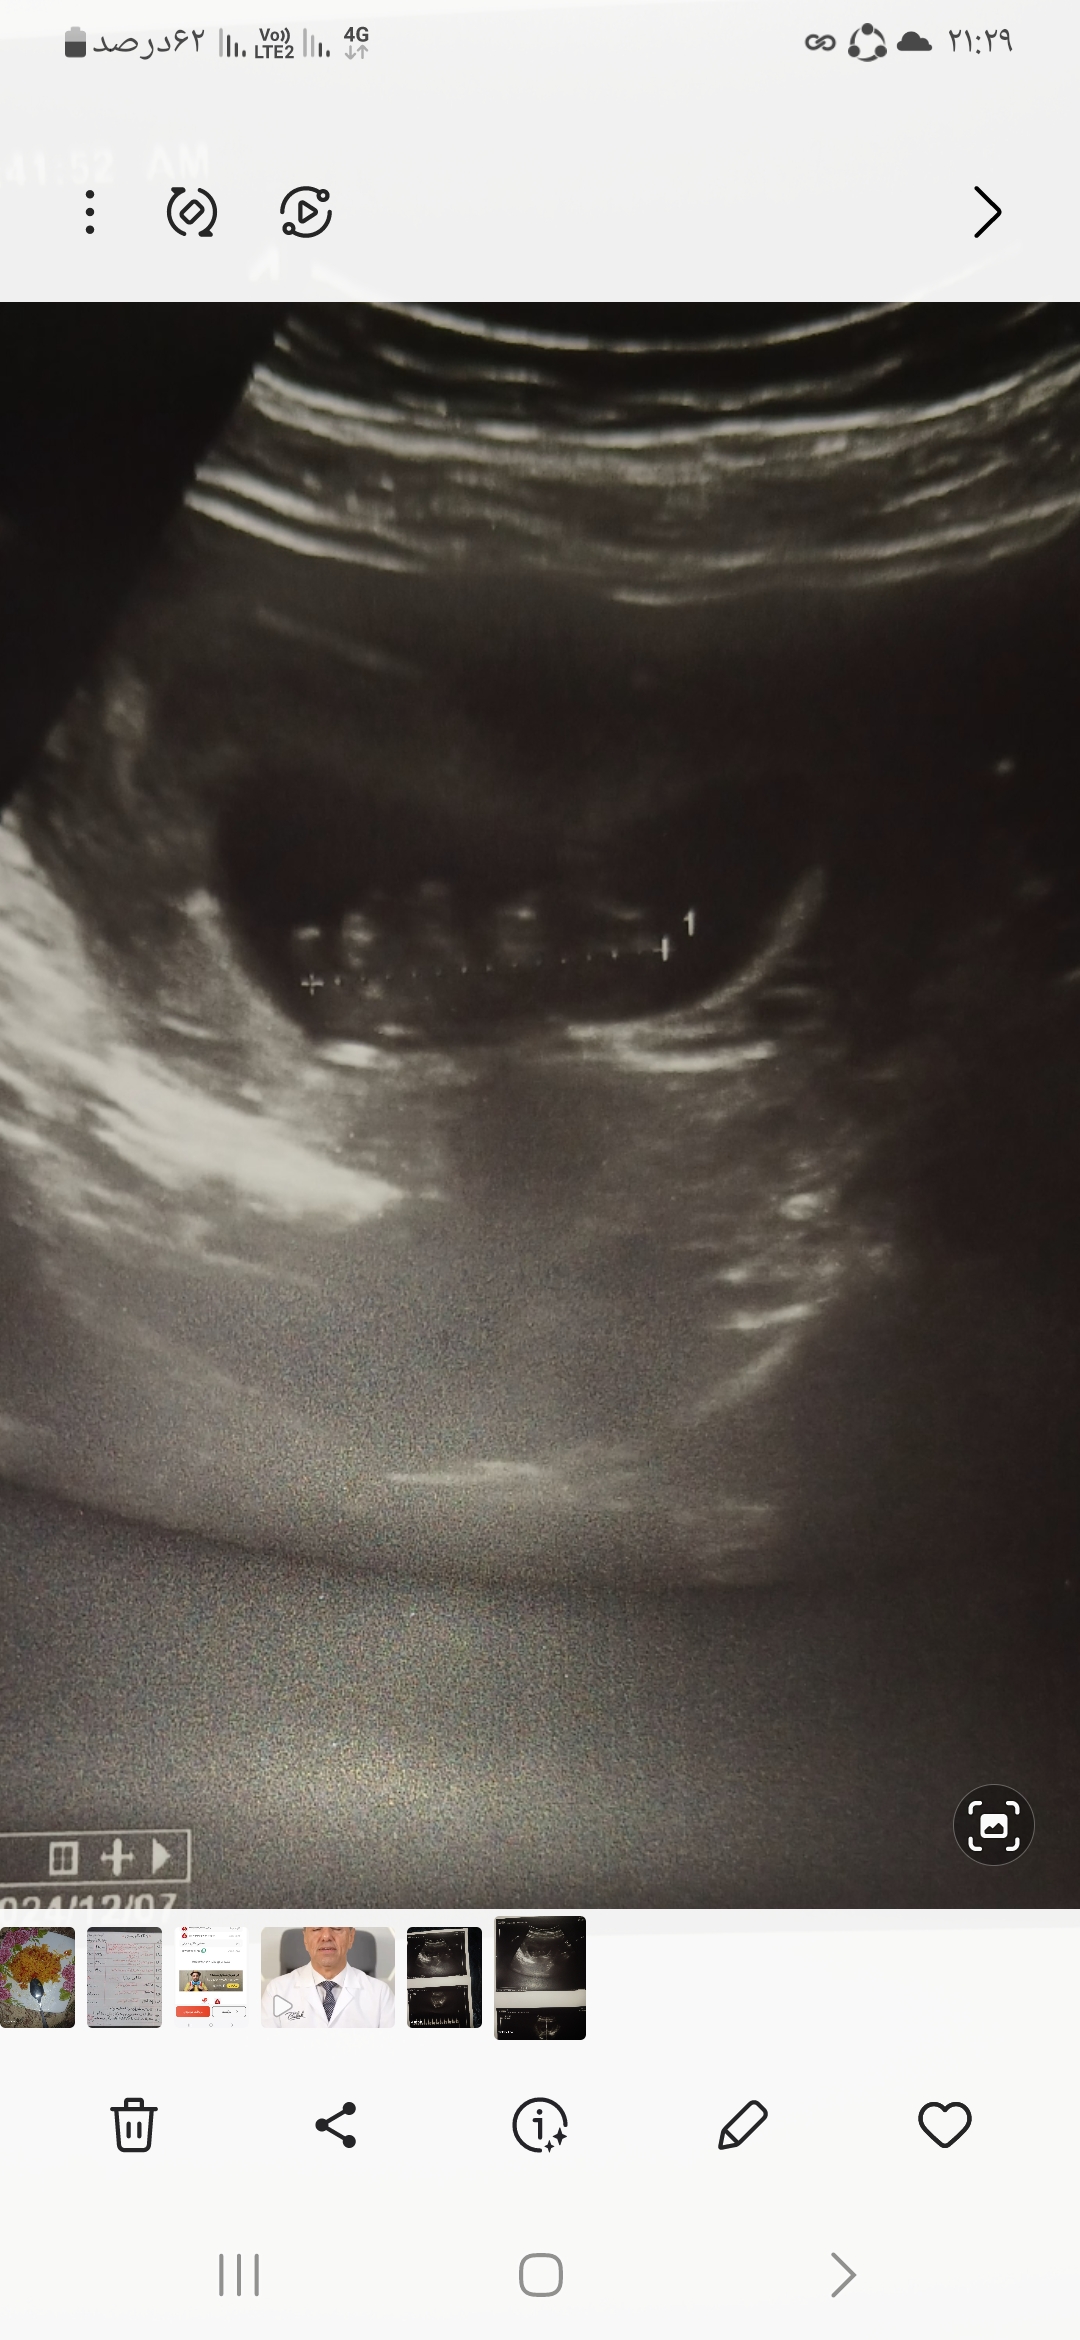

mtoofani مدیر استارتر عضویت: 1400/04/07 تعداد پست: 927 عنوان بارداری 60 بازدید | 2 پست کی میتونه از سونو ۱۰هفته جنسیت جنین تشخیص بده 1404/05/20 | 21:28 0 نفر لایک کرده اند ... گزارش تاپیک نامناسب